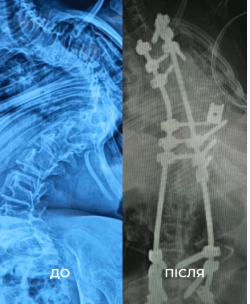

Дівчинка Віка зі Східниці, яку прооперували у лікарні Святого Миколая у Львові, мала проблеми з хребтом з раннього дитинства. Ще у 6 місяців через вигинання хребта її мама звернулася до лікарів. Ті діагностували рідкісне генетична захворювання — міопатію Бетлема. До 12 років у дитини вже був сколіоз найвищого четвертого ступеня. Її хребет викривився на 160 градусів. Вдома дівчинці доводилося пересуватися на ходунцях, а в школі — на кріслі колісному.

До та після

“Щоб виправити її сколіоз, нам потрібно було видалити цілий хребець. У перший день операції ми закріпили її хребет гвинтами. А потім уже на другий день видалили кілька ребер, ізолювали спинний мозок та встановили титанову клітку для підтримки хребта. А потім повільно виправляли її разом з моєю колегою, нейрофізіологинею Меган Маллані”, — розповів американський ортопед Марк Диржка.

Два тижні після операції дівчинка пробула під киснем в реанімації. Але, як стверджують самі ортопеди, це вартувало таких зусиль. Хребет Віки виправився на 85%. Вона тепер не відчуватиме болю та задишки. Мама має надію, що дівчинка зможе бігати з однолітками.